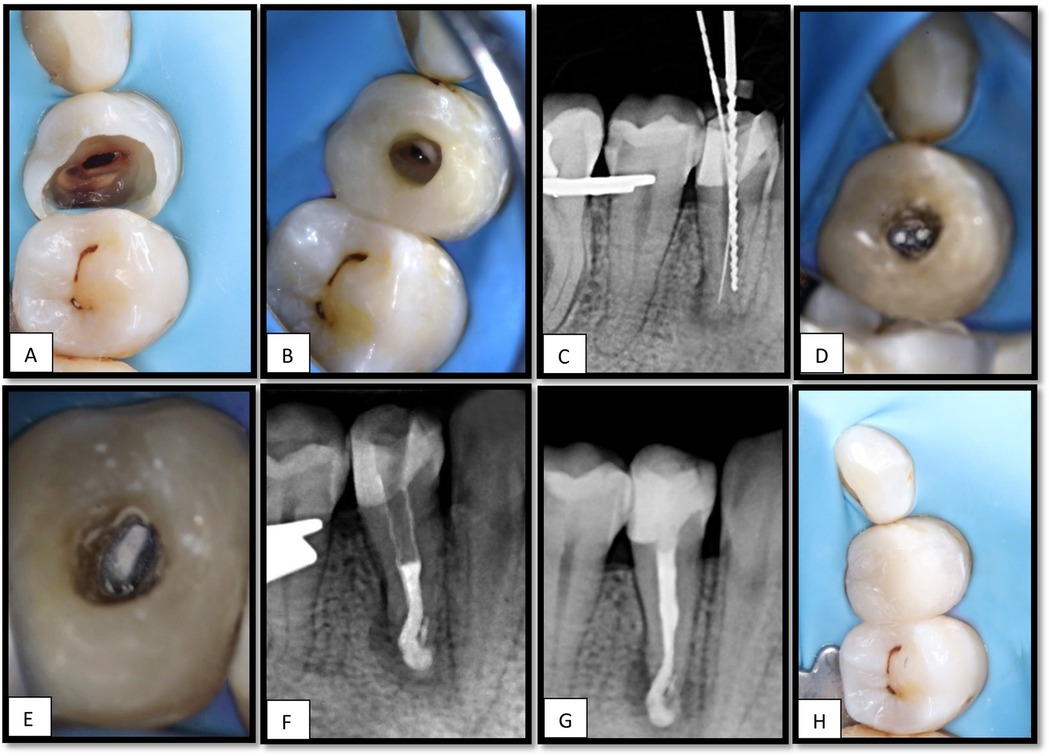

The patient was reported to be medically fit, American Society of Anesthesiologists (ASA) class I (13), and had no medications or allergies. The patient's dental history revealed prior orthodontic treatment 6 years previously for 3 years, there was no history of dental trauma. Upon examination, the tooth exhibited no sensitivity to percussion or palpation, no swelling, no sinus tract was observed, the probing depth was normal (2 mm), and both tooth mobility and gingival consistency were normal. Tooth #44 was restored with a temporary filling. Teeth #43 and #45 were present and exhibited normal proximal contact with tooth #44 (Figure 1A). Radiographic assessment revealed periapical radiolucency at the apex of tooth #44 with evidence of root resorption in the apical third of the same tooth (Figure 1B). The crestal bone height was within normal limits.

Figure 1. (A) Intraoral image for tooth#44. (B) intraoral periapical radiograph shows a periapical radiolucency associated with the apex of tooth #44, (C) an axial view of CBCT shows apical radiolucency (RL) associated with the apex of tooth #44 with signs of internal and external resorption. (D,E), RL extending to tooth #43. (F,G), sagittal and coronal views for tooth #44 (H), sagittal view for tooth #43 showing apical radiolucency.

Cone-beam computed tomography (CBCT) revealed internal and external root resorption in the apical portion of the root (Figures 1C–G), and radiolucency extending to the apex of tooth # 43 (Figures 1D–H).